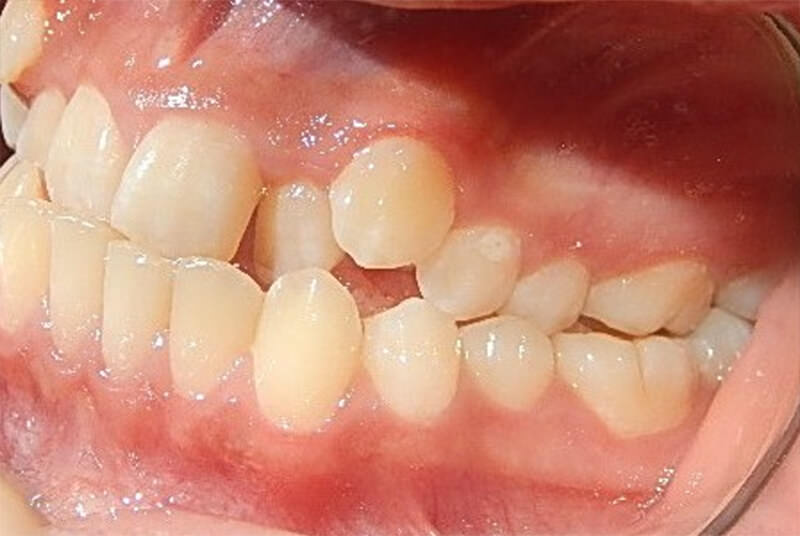

En la de frente se muestra, la línea media dental inferior (línea roja) desviada 2mm hacia la derecha con relación a la línea media dental superior (línea negra) (figura 3). En las del lado derecho e izquierdo en oclusión la relación clase III molar y canina II bilateral. La relación de overbite negativo al igual como mordida cruzada posterior bilateral y mordida cruzada anterior (figuras 4 y 5)

Fig. 4 Derecha

Fig. 5 Intraoral izquierda